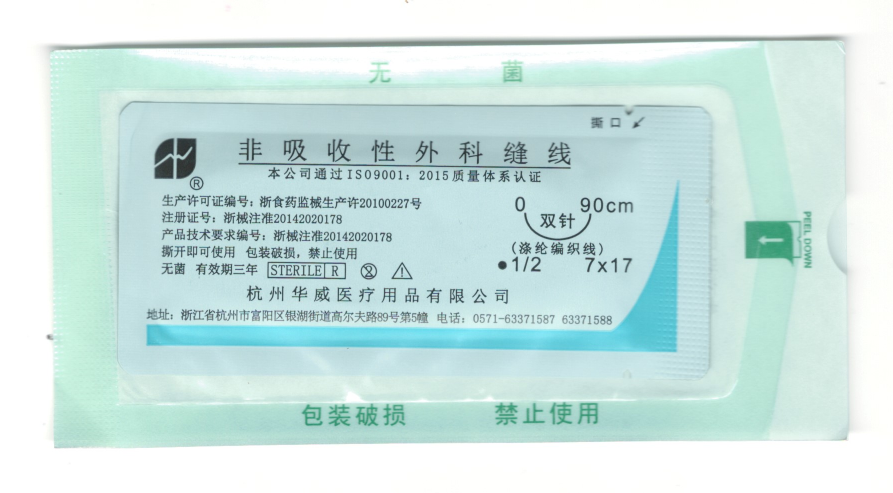

非吸收性外科縫線1